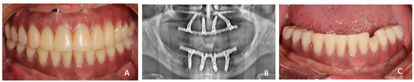

医嘱要求戴牙后1、3、6个月、1年、每半年定期复诊维护,口腔卫生指导,检查修复体、修复配件完整性和稳固性,清洁义齿和基台周围,修理修复体出现的裂纹或折裂部分,检查并局部调整咬合。种植修复后3年X线检查示种植体周围骨结合良好,种植体周围未见明显边缘骨吸收(图16,图17)。

种植修复后义齿使用状况良好,经过治疗周期内多次的健康教育,患者掌握了口腔卫生理念和健康行为,口腔卫生状况改善。植体周健康状况保持良好。通过治疗恢复了相对健康的口腔环境和牙列的完整性,美学效果及咬合功能患者满意(图18)。